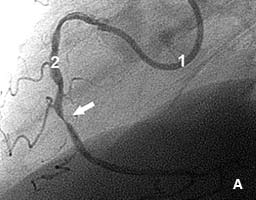

Пациент с жалобами на боли в сердце после незначительной физической нагрузки.

На коронарограмме (рис 5а) - субтотальный стеноз правой коронарной артерии.

В место стеноза установлен коронарный стент. Стеноз полностью устранен (рис.5б).

Боли прекратились сразу же после стентирования.

Рис.5 Стеноз правой коронарной артерии до (А) и после (Б) стентирования.

1 - катетер; 2 - контрастированная коронарная артерия; стрелкой отмечена зона стеноза. |